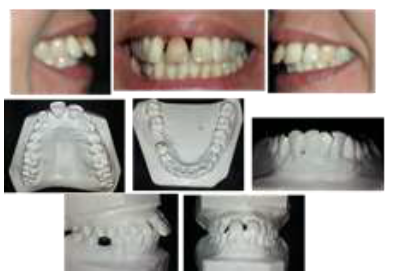

En el examen clínico se detectaron rasgos y anomalías (Figura 1) que se consideraron en la toma de decisiones durante el tratamiento, los cuales se exponen a continuación.

Intraorales: Arcada superior: Dientes presentes de 18 a 28. Restaurados: 160, 11IP, 12I 24od, 26od, 27o.11 tratamiento endodóntico realizado y discromía. Malposición dentaria. Vestibuloversión, extrusión y mesoversión de incisivos. Diastemas 12-11 de 3 mm, y 11-21 de 2 mm. Corona clínica aumentada, Movilidad grado III de 11 y grado II de 12, migración patológica periodontal; expuesto cemento en 11 y 21 (3 mm). Encías de coloración normal. Biotipo periodontal con margen gingival delgado y marcadamente festoneado.5 Falta de la papila interdentaria entre 11 y 21.

Arcada inferior: extraído 46. Malposición dentaria: vestibuloversión de incisivos, 44RML, 43MV, 31RML, 33RMV, 34RML. Movilidad dentaria grado II en incisivos, 44 y 47; resto de los dientes grado I.

Arcadas en oclusión: Relación Antero posterior: Relación molar: neutroclusión izquierda, derecha no clasificable. Relación canina neutroclusión bilateral. Resalte 8 mm, curva de Spee aumentada.

Transversal: Línea media superior desviada a la izquierda 3 mm. Resalte posterior normal.

Vertical: Sobrepase 1/3 corona

Examen oclusal funcional: trauma oclusal interincisivo en oclusión céntrica. En movimiento de protrusión, desoclusión posterior exagerada por acentuación de la curva de Spee, ausencia de movimientos de lateralidad.

Clasificación sindrómica: Síndrome de clase I

Discrepancia hueso diente superior = 3,8 mm, Inferior= -1,9 mm

Al sondaje no sangramiento ni bolsas de 4 mm o más.

El tratamiento duró 18 meses y se consideró exitoso debido a que se consiguieron los objetivos planteados al inicio del mismo. Los resultados se describen a continuación (Figura 2).

Se observa alineación dentaria superior e inferior, disminución de la corona clínica y resalte normal.

Se mantuvo la estética facial sobre todo de la zona de los labios. Mejoró la sonrisa y la exposición gingival.

Se redujo la protrusión y proinclinación superior e inferior, se cerraron los espacios interdentales. Se corrigieron las malposiciones dentarias, mejoró la extrusión dental anterior.

Se consiguió una oclusión funcional, sin contactos exagerados en céntrica, con guía incisiva en movimientos protrusivos y función en grupo bilateral.

Hubo un incremento considerable en la inserción periodontal, con una disminución de la movilidad dentaria, la cual se redujo a grado I en todos los dientes con una movilidad inicial mayor y se eliminó en el resto. Se mantuvo la integridad del periodonto de protección. Se recuperó la forma de las papilas interdentales.